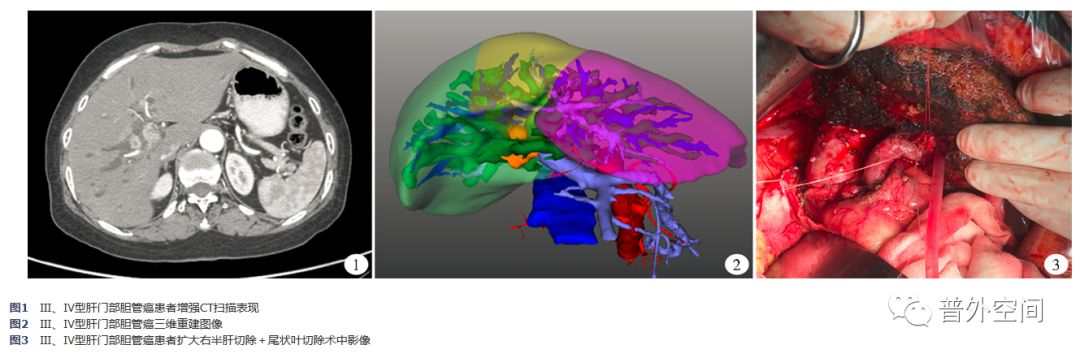

根据术前影像学资料(主要是CT、直接胆道造影或三维可视化重建)判断肿瘤分型(图1、图2)。肿瘤分型采用Bismuth-Corlette分型与Starzl扩充分型相结合的方式。扩大肝切除组Ⅲa型2例,Ⅲa+、Ⅳa、Ⅳb型均为4例,Ⅲb型8例,Ⅲb+、Ⅳ型均为3例,Ⅴ型1例。局限肝切除组Ⅲa型9例,Ⅲb型12例,Ⅳ型8例,Ⅲa+型3例,Ⅲb+、Ⅳa、Ⅳb型均为4例。两组患者肿瘤分型差异无统计学意义(P>0.05)。

扩大肝切除组主要根据Starzl扩充分型及肿瘤浸润情况行手术治疗方式的选择。水平切断远端胆总管,距离肿瘤边缘>5 mm,残端封闭,肝切除范围是半肝及以上肝切除和(或)联合尾状叶切除。故有6例行右半肝加尾状叶切除术,8例行扩大右半肝加尾状叶切除术,6例行左半肝切除术,6例行左半肝加尾状叶切除术,3例行扩大左半肝切除术(图3)。局限肝切除组切断远端胆总管,残端封闭,不规则切除肝门处肝组织,标本送病理。